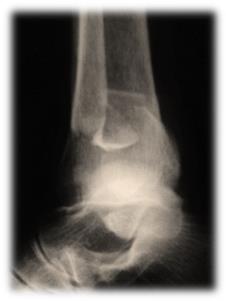

Пациент С. 64 лет, страдающий диабетом II типа, тяжелое течение. Закрытый перелом наружной внутренней лодыжек. Малоинвазивный остеосинтез лодыжек.

Рисунок 3Рисунок 4Рисунок 5(а)Рисунок 5(б)Рисунок 6 (а,б) Результат через 6 недель после операции.